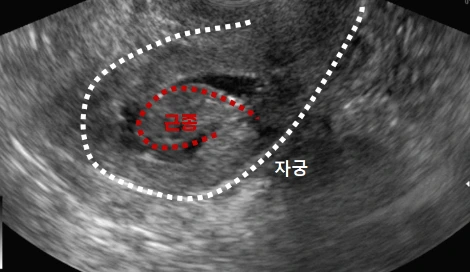

초음파에서 용종 혹은 근종으로 생각되는 자궁 내부에 위치하는 병변

난임, 과다월경 및 과도한 질 출혈, 반복적인 초기 유산의 원인으로 생각되는 점막하 자궁근종은 자궁경 수술을 통해서 제거할 수 있습니다. 초음파에서 점막하 자궁근종으로 확인되면 대개 자궁경을 이용하여 제거를 시도하게 되는데, 크기가 4-5cm 이상이라면 수술시간이 많이 길어지기 때문에 자궁경 수술로 시행하는 게 오히려 안 좋을 때도 있습니다.